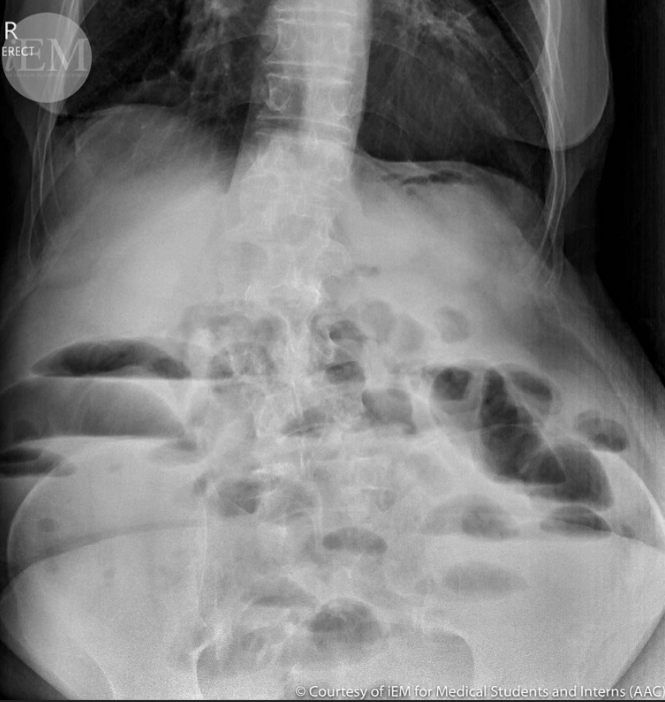

42세 여성이 복통과 지속적인 구토를 호소하며 병원에 내원했다. 환자는 3년 전 급성 충수염으로 인해 충수절제술을 받은 병력이 있다. 복부 평면 X선 촬영 결과이다. 초기 치료 방법은 무엇인가?

• 복부 수술력이 있는 환자가 복통/구토를 주소로 내원, AXR상 multiple air-fluid level이 관찰되므로 기계적 장폐색이 의심된다.

• 응급수술의 적응증에 해당하는 중증 감염 소견이나 복막자극징후는 주어지지 않았으므로, L-tube insertion을 통한 decompresesion 및 수액요법 등 보존적 치료가 기본이다.